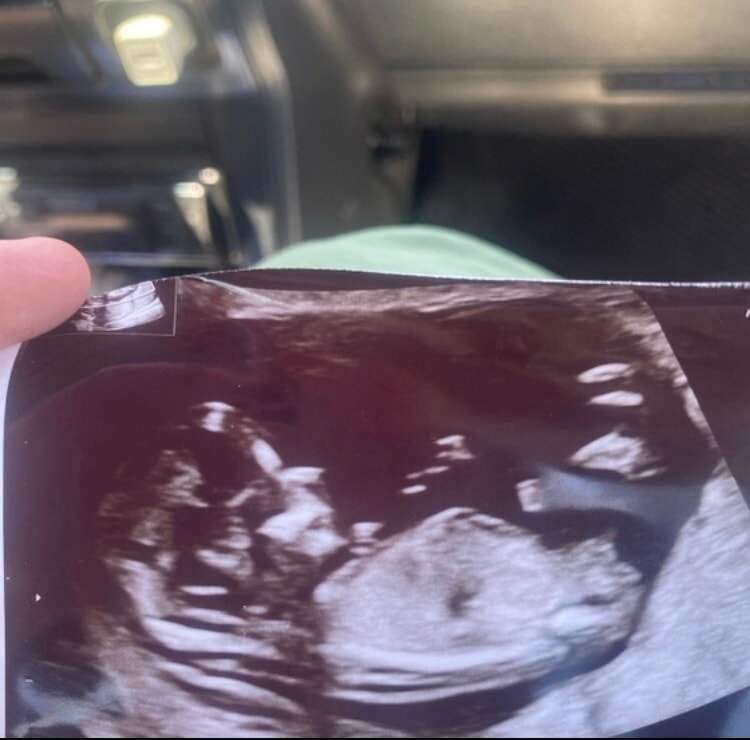

asel, у меня вот так , и я надеюсь на мальчика после 3-х девочек😅 Изображение

Нина, у вас чуть наверх смотрит это угол)походу мальчик

Деля , а был такой неделю назад на бесплатном скрининге😁 Изображение

asel, тут на мальчика похож )только половой бугорок легко перепутать с пуповиной

Деля , блин я вас не понимаю вы на какой снимок отвечаете?😁первый снимок это сегодняшний там нет ничего мальчиковского)а на втором да на мальчика похож )это неделю назад было

asel, который неделю назад